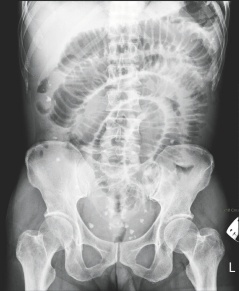

臺(tái)南市55歲女子腹中取出29顆大大小小的“蛋”,從X光上可看到腹中滿(mǎn)布點(diǎn)狀的白色物體。

這名女子最近因腹痛、嘔吐而到成大急診就醫(yī),醫(yī)師從X光檢查中,發(fā)現(xiàn)腹腔內(nèi)有許多白點(diǎn)狀的物體,原本以為是糞石或食物堆積在腸道中,經(jīng)緊急開(kāi)刀,發(fā)現(xiàn)這些物體是在腸子外,而非腸子里,醫(yī)師共取出大大小小共29顆,色白、外形橢圓,很像蛋一般,材質(zhì)卻像橡膠一般有彈性。